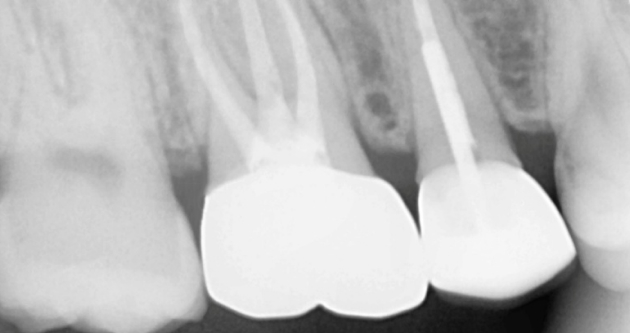

실제 사례 Before & After

바른선택치과의원은 결과로 증명합니다. 기능과 심미 모두 찾은 바른선택치과의원 실제 환자 케이스를 확인해보세요.

before Before

after After

치료 시작 전 촬영 2025.02.18 | 치료 완료 후 촬영 2025.02.28

※ 바른선택치과의원은 의료법을 준수하며 위 케이스는 실제 내원 환자분의 동의하에 공개된 사진과 동일한 환자분께 같은 조건에서 촬영한 사진을 활용했습니다.

개인에 따라 진료 및 치료 방법이 다르게 적용할 수 있으며, 효과와 부작용이 개인마다 다르게 나타날 수 있는 점을 안내해 드리며, 진료 전 전문의료진과 충분한 상담을 권해드립니다.